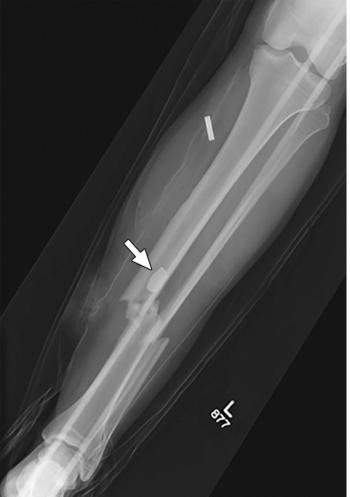

Analysis of imaging performed immediately following the Boston Marathon bombings allowed researchers to improve the emergency response system.